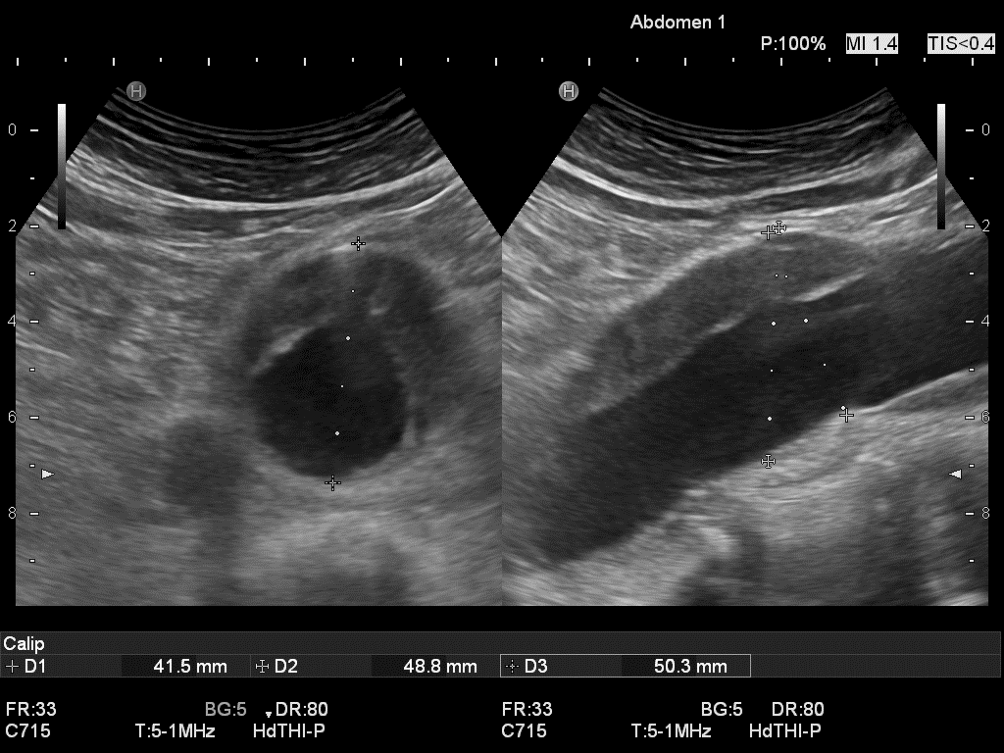

Abb. 1

Aortendurchmesser beim abdominalen Aortenaneurysma (AAA) mit Elongation nach links-lateral: Vergleich der axialen Messung im Oberbauchquerschnitt (links Durchmesser/D1 [in schräg transversaler Messachse] von 57 mm → Operationsindikation) mit der orthogonalen Messung, in welcher der Transducer an gleicher Stelle senkrecht zur Gefäßachse gedreht wurde (b/D2 von 47 mm und fast Rundstruktur → keine Operationsindikation). Diese orthogonale Durchmesserbestimmung (rechts) entspricht dem reellen Durchmesser (vgl. Videoclip 1). Der anterior-posteriore (a.-p.) Durchmesser ist gleichbleibend (44 mm bzw. 45 mm in D 3 und D 4)